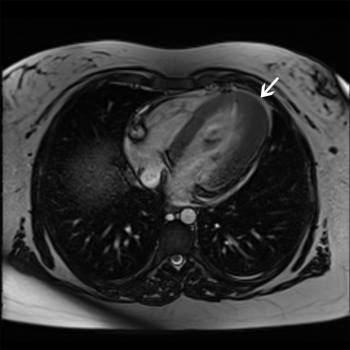

Chez les patients atteints d’une cardiomyopathie

hypertrophique obstructive (CMHO), l’objectif primordial du

traitement est l’amélioration des symptômes qui hypothèquent

lourdement la qualité de vie et ses multiples dimensions. La

pharmacothérapie actuelle repose sur des médicaments qui ne sont en

aucun cas spécifiques de la pathogénie sous-jacente.